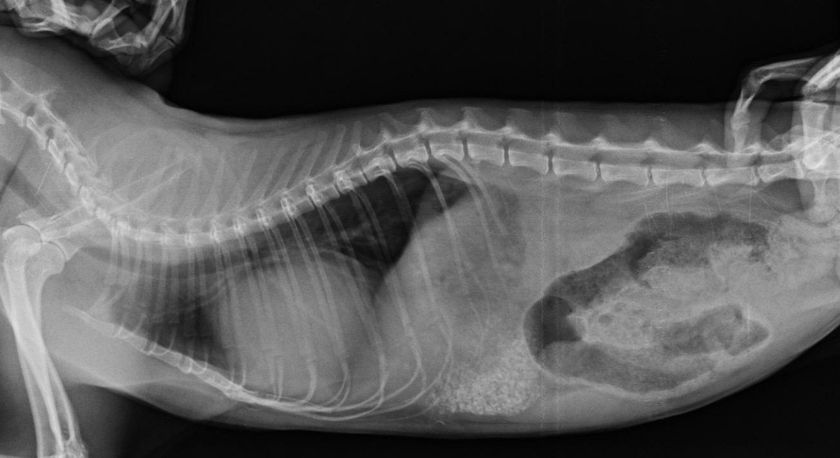

Диагностировать дефект проблематично, без аппаратных исследований не обойтись. На УЗИ монитор показывает расплывчатые затемнения. Чтобы подтвердить диафрагмальную грыжу у кошки, требуется рентгенография. Кошке дают корм с барием, затем делают рентгеновские снимки.

с данной патологией усатые питомцы могут уже рождаться, но в большинстве случаев они приобретенные вследствие серьезных травм, падений с высоты, ударов и т.п. Из-за повышения внутрибрюшного давления кишечник начинает усиленно давить на диафрагму, прорывая ее все сильнее и давя на органы грудной полости. Очень сложно диагностировать, т.к. из-за особенностей анатомического строения у кошек даже на УЗИ и рентгене точно грыжевого мешка не видно, кроме затемнения общего плана. Чтобы убедиться, что у кошки именно диафрагмальная грыжа, ее пытаются накормить контрастным веществом (каша с барием) и сделать в нужное время рентген. Опасный вид патологии, может привести к гибели питомца.

Диафрагмальная грыжа у кошки

Чаще всего диафрагмальная грыжа у кошки является приобретенной, например, после падения котенка. Данный дефект отчетливо виден при рентгенологическом исследовании – внутренние органы буквально вдавливаются в диафрагму, тем самым растягивая и разрывая ее. Также диафрагмальная грыжа у кошки может быть выявлена не сразу, а только после того, как животное поело бариевую кашицу. Только после этого возможно повторное исследование.